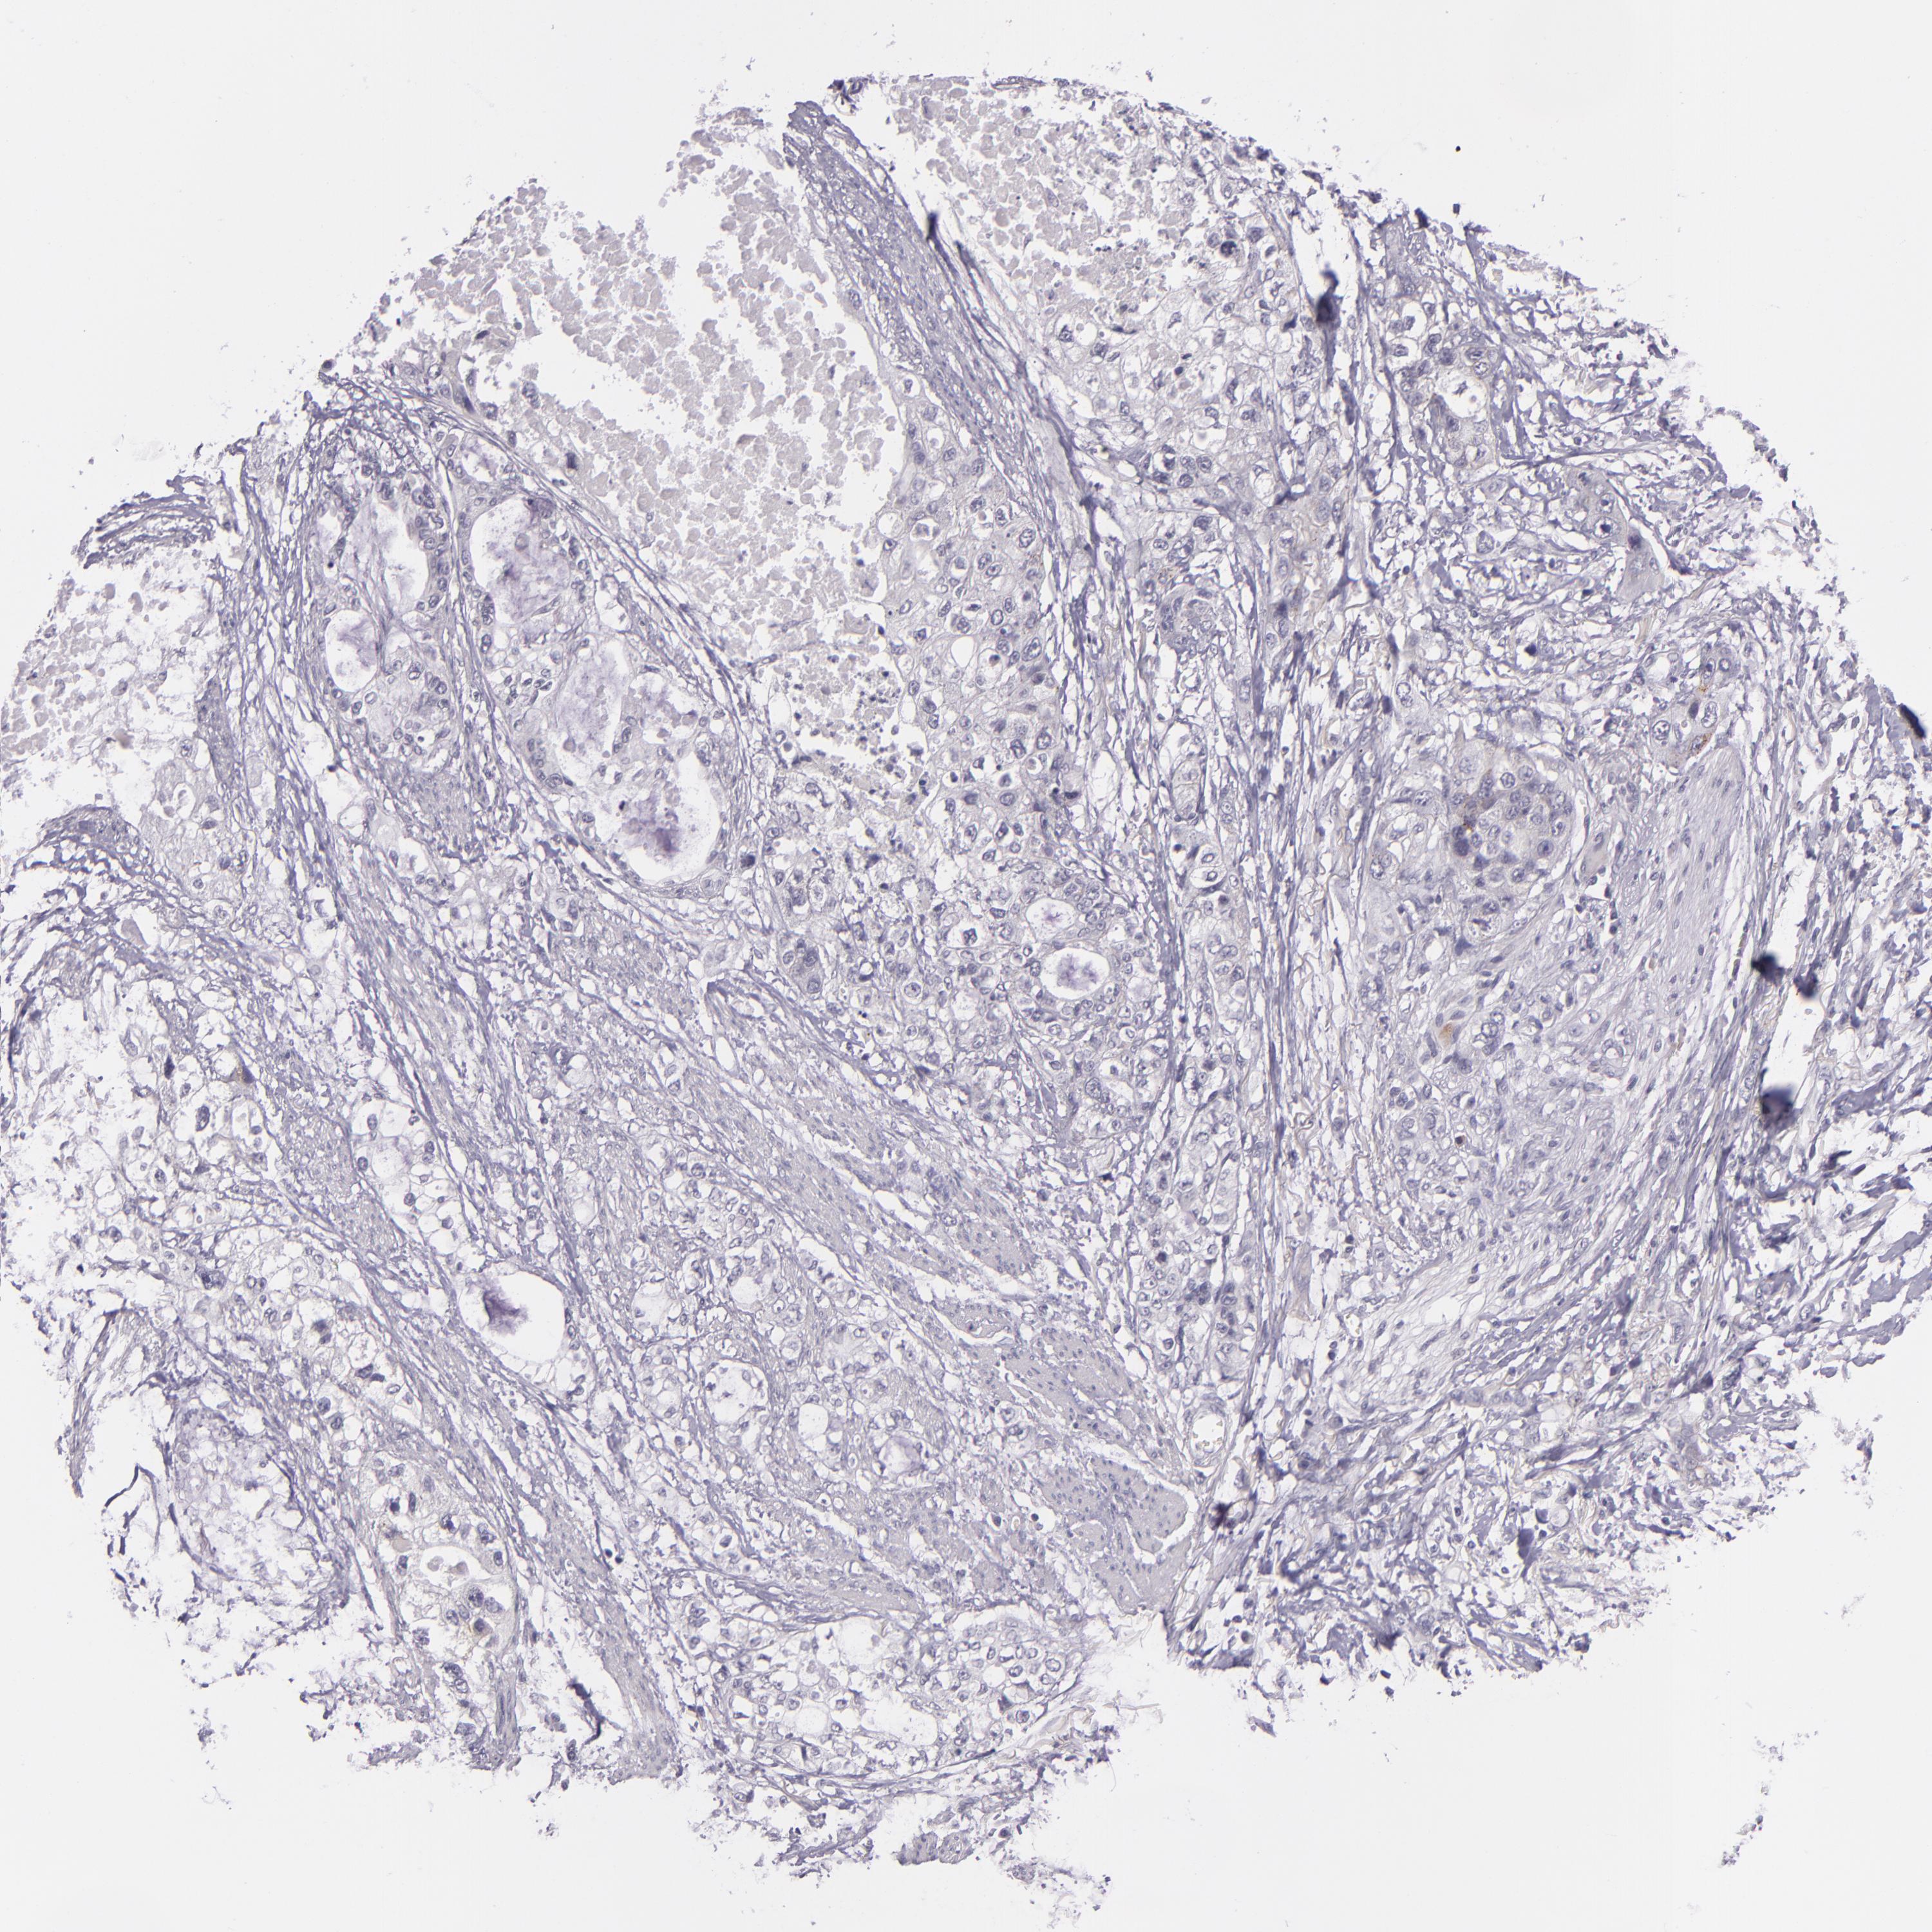

STOMACH CANCER - Protein expressioni

A mouse-over function shows sample information and annotation data. Click on an image to view it in a full screen mode. Samples can be filtered based on level of antibody staining by selecting one or several of the following categories: high, medium, low and not detected. The assay and annotation is described here.

Note that samples used for immunohistochemistry by the Human Protein Atlas do not correspond to samples in the TCGA dataset.

Antibody stainingi

Antibody staining in the annotated cell types in the current human tissue is reported as not detected, low, medium, or high, based on conventional immunohistochemistry profiling in selected tissues. This score is based on the combination of the staining intensity and fraction of stained cells.

Each image is clickable and will lead to virtual microscopy that enables deeper exploration of all samples and also displays staining intensity scores, fraction scores and subcellular localization as well as patient and tissue information for each sample.

Antibody CAB001960

Antibody CAB016353

Staining

High

Medium

Low

Not detected

Intensity

Strong

Moderate

Weak

Negative

Quantity

>75%

75%-25%

<25%

None

Location

Nuclear

Cytoplasmic/membranous

Cytoplasmic/membranous,nuclear

Adenocarcinoma, NOS

Adenocarcinoma, High grade